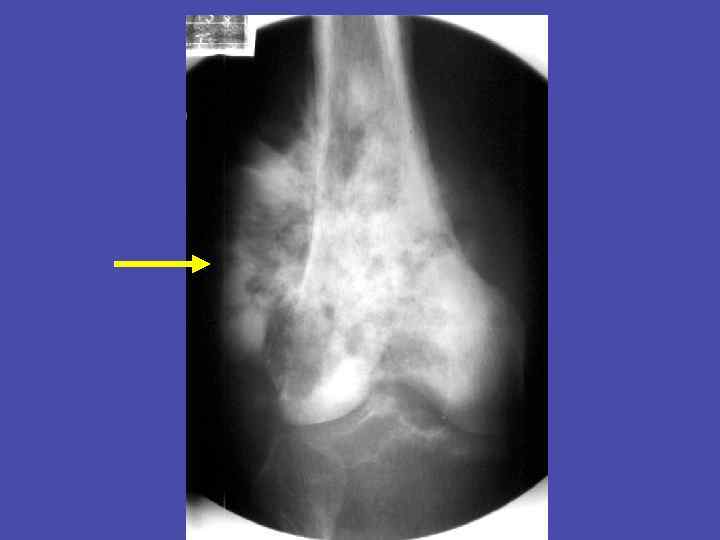

Периостит, деструкция метадиафиза, перфорационные отверстия плечевой кости 35

Перфорационные отверстия большеберцовой кости 36